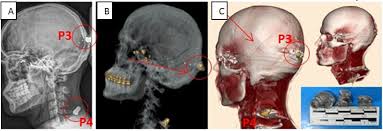

É a aplicação das técnicas de imagem médica — como radiografia, tomografia e até ressonância — no contexto legal e criminal. Com ela, é possível analisar traumas, balísticas, identificar corpos e reconstruir eventos ligados à causa da morte ou ferimentos.

- ✔️ Localização de projéteis e objetos metálicos

- Solução de crimes com auxílio de reconstruções tomográficas